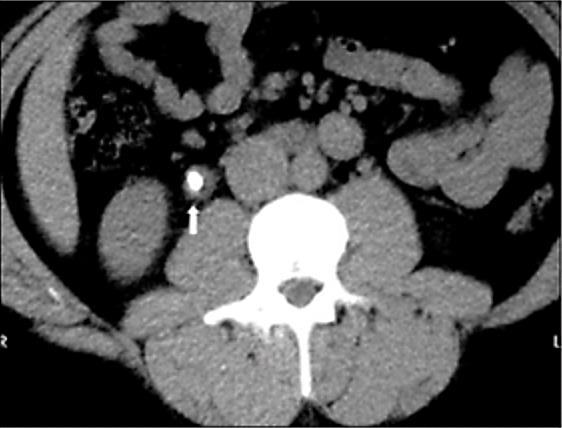

Mulher, 78 anos, portadora de hipertensão arterial sistêmica, diabetes mellitus tipo 2, doença renal crônica estágio II (creatinina basal 0,8 mg/dL), infarto agudo do miocárdio há dois anos com necessidade de angioplastia e tratamento de infecção urinária por uma Serratia sp. produtora de ESBL (Beta-Lactamase de Espectro Estendido) há seis meses. Refere há dez dias disúria e polaciúria, evoluindo há três dias com lombalgia à direita e febre aferida de 38,2ºC. Dá entrada na sala de emergência confusa, hipotensa, taquicárdica, tempo de enchimento próximo a três segundos, levemente taquipneica, sem desconforto, porém com dor à palpação difusa de abdome, pior em fossa ilíaca direita. Coletadas hemocultura, urocultura e exames séricos na urgência. Você chega para o plantão noturno e o plantonista do dia te mostra a tomografia recém realizada (Figura 10) e refere que não teve tempo de checar os exames laboratoriais ou prescrever antibiótico para a paciente.

Hb 14,0 g/dL; Leucócitos 16.500 mil/mm3 com desvio até metamielócitos; Ureia 102 mg/dL; Cr 1,80 mg/dL; Sódio 139 mEq/L; Potássio 5,1 mEq/L; Bilirrubina Total 1,2 mg/dL; Bilirrubina Indireta 0,20 mg/dL; Bilirrubina Direta 1,0 mg/dL; TGO 45 U/L (< 31 U/L); TGP 40 U/L (< 31 U/L); Gama-GT 32 U/L (5 - 36 U/L); Fosfatase Alcalina 67 U/L (35 - 104 U/L); Albumina 3,7 g/dL (3,4 - 4,8 g/dL); INR 1,1.

Enunciado 3340355-1

Figura 10. Tomografia computadorizada sem contraste de abdome

Assinale a alternativa com a conduta mais adequada para este paciente neste momento.